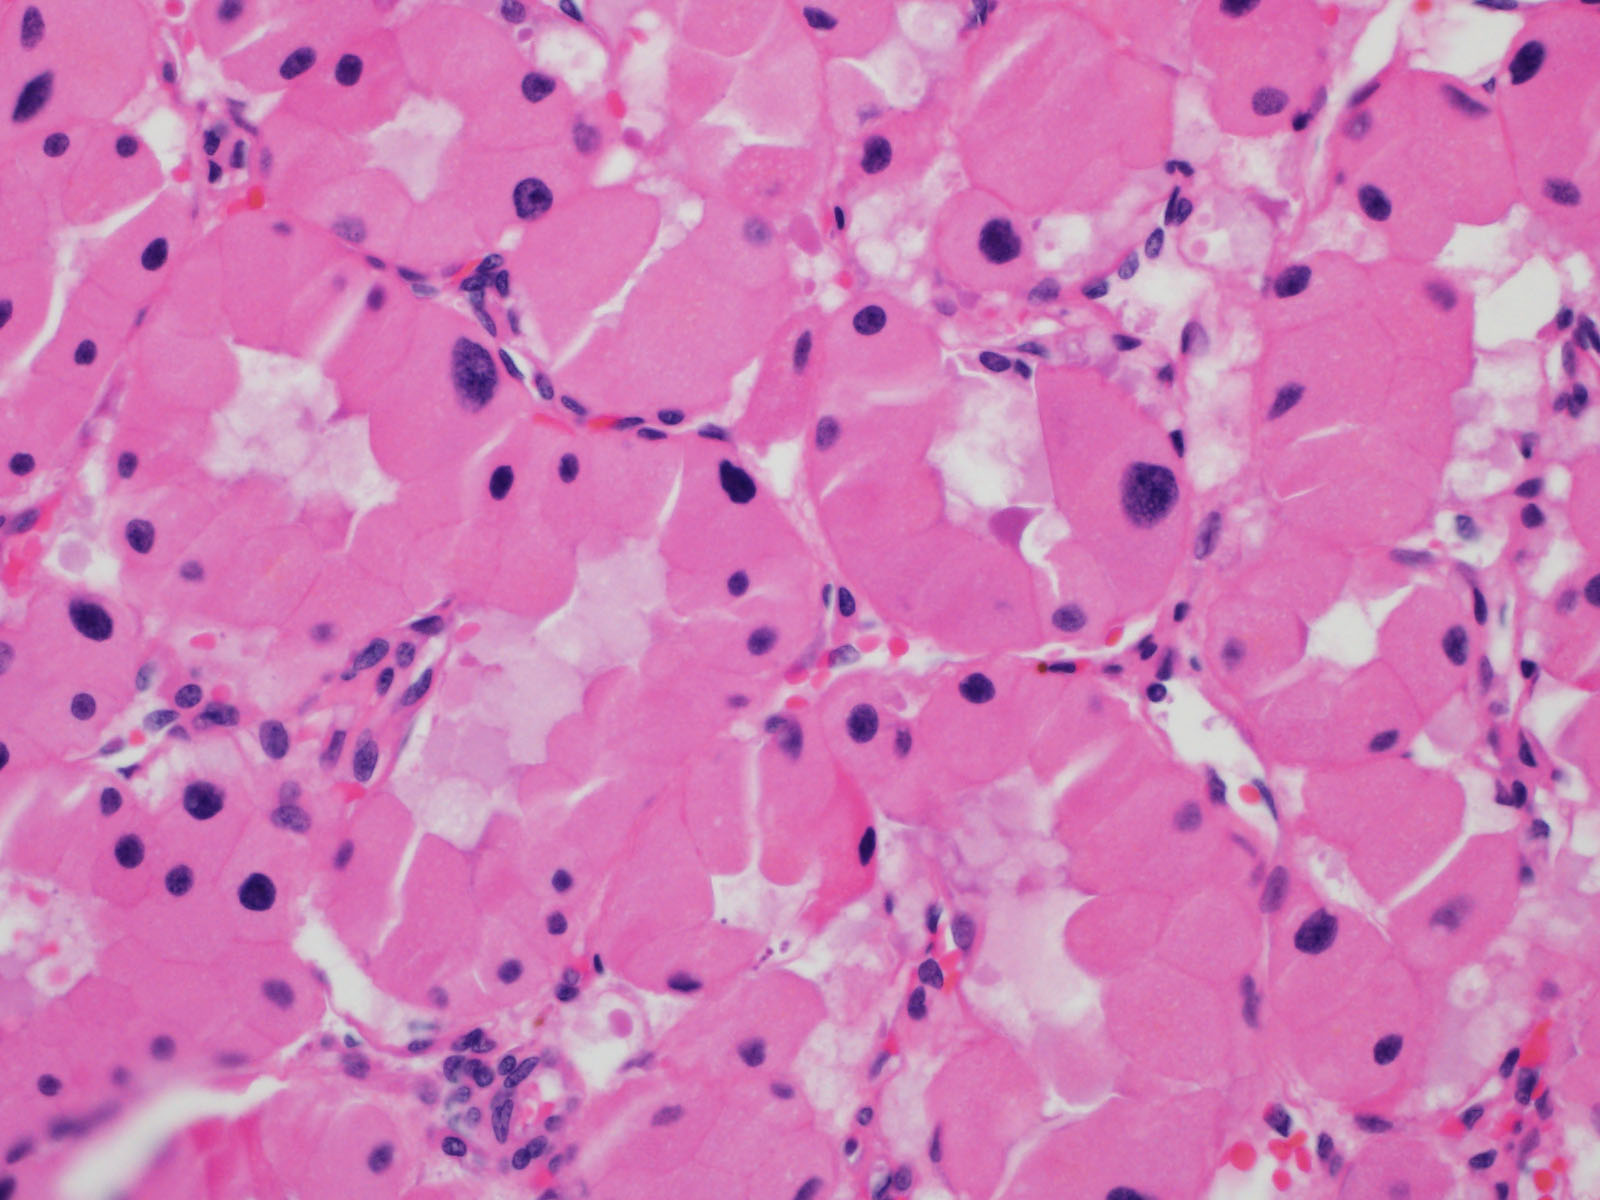

Case ID: 757

Consensus grade: I would not grade this tumor

Case description (by case creator):